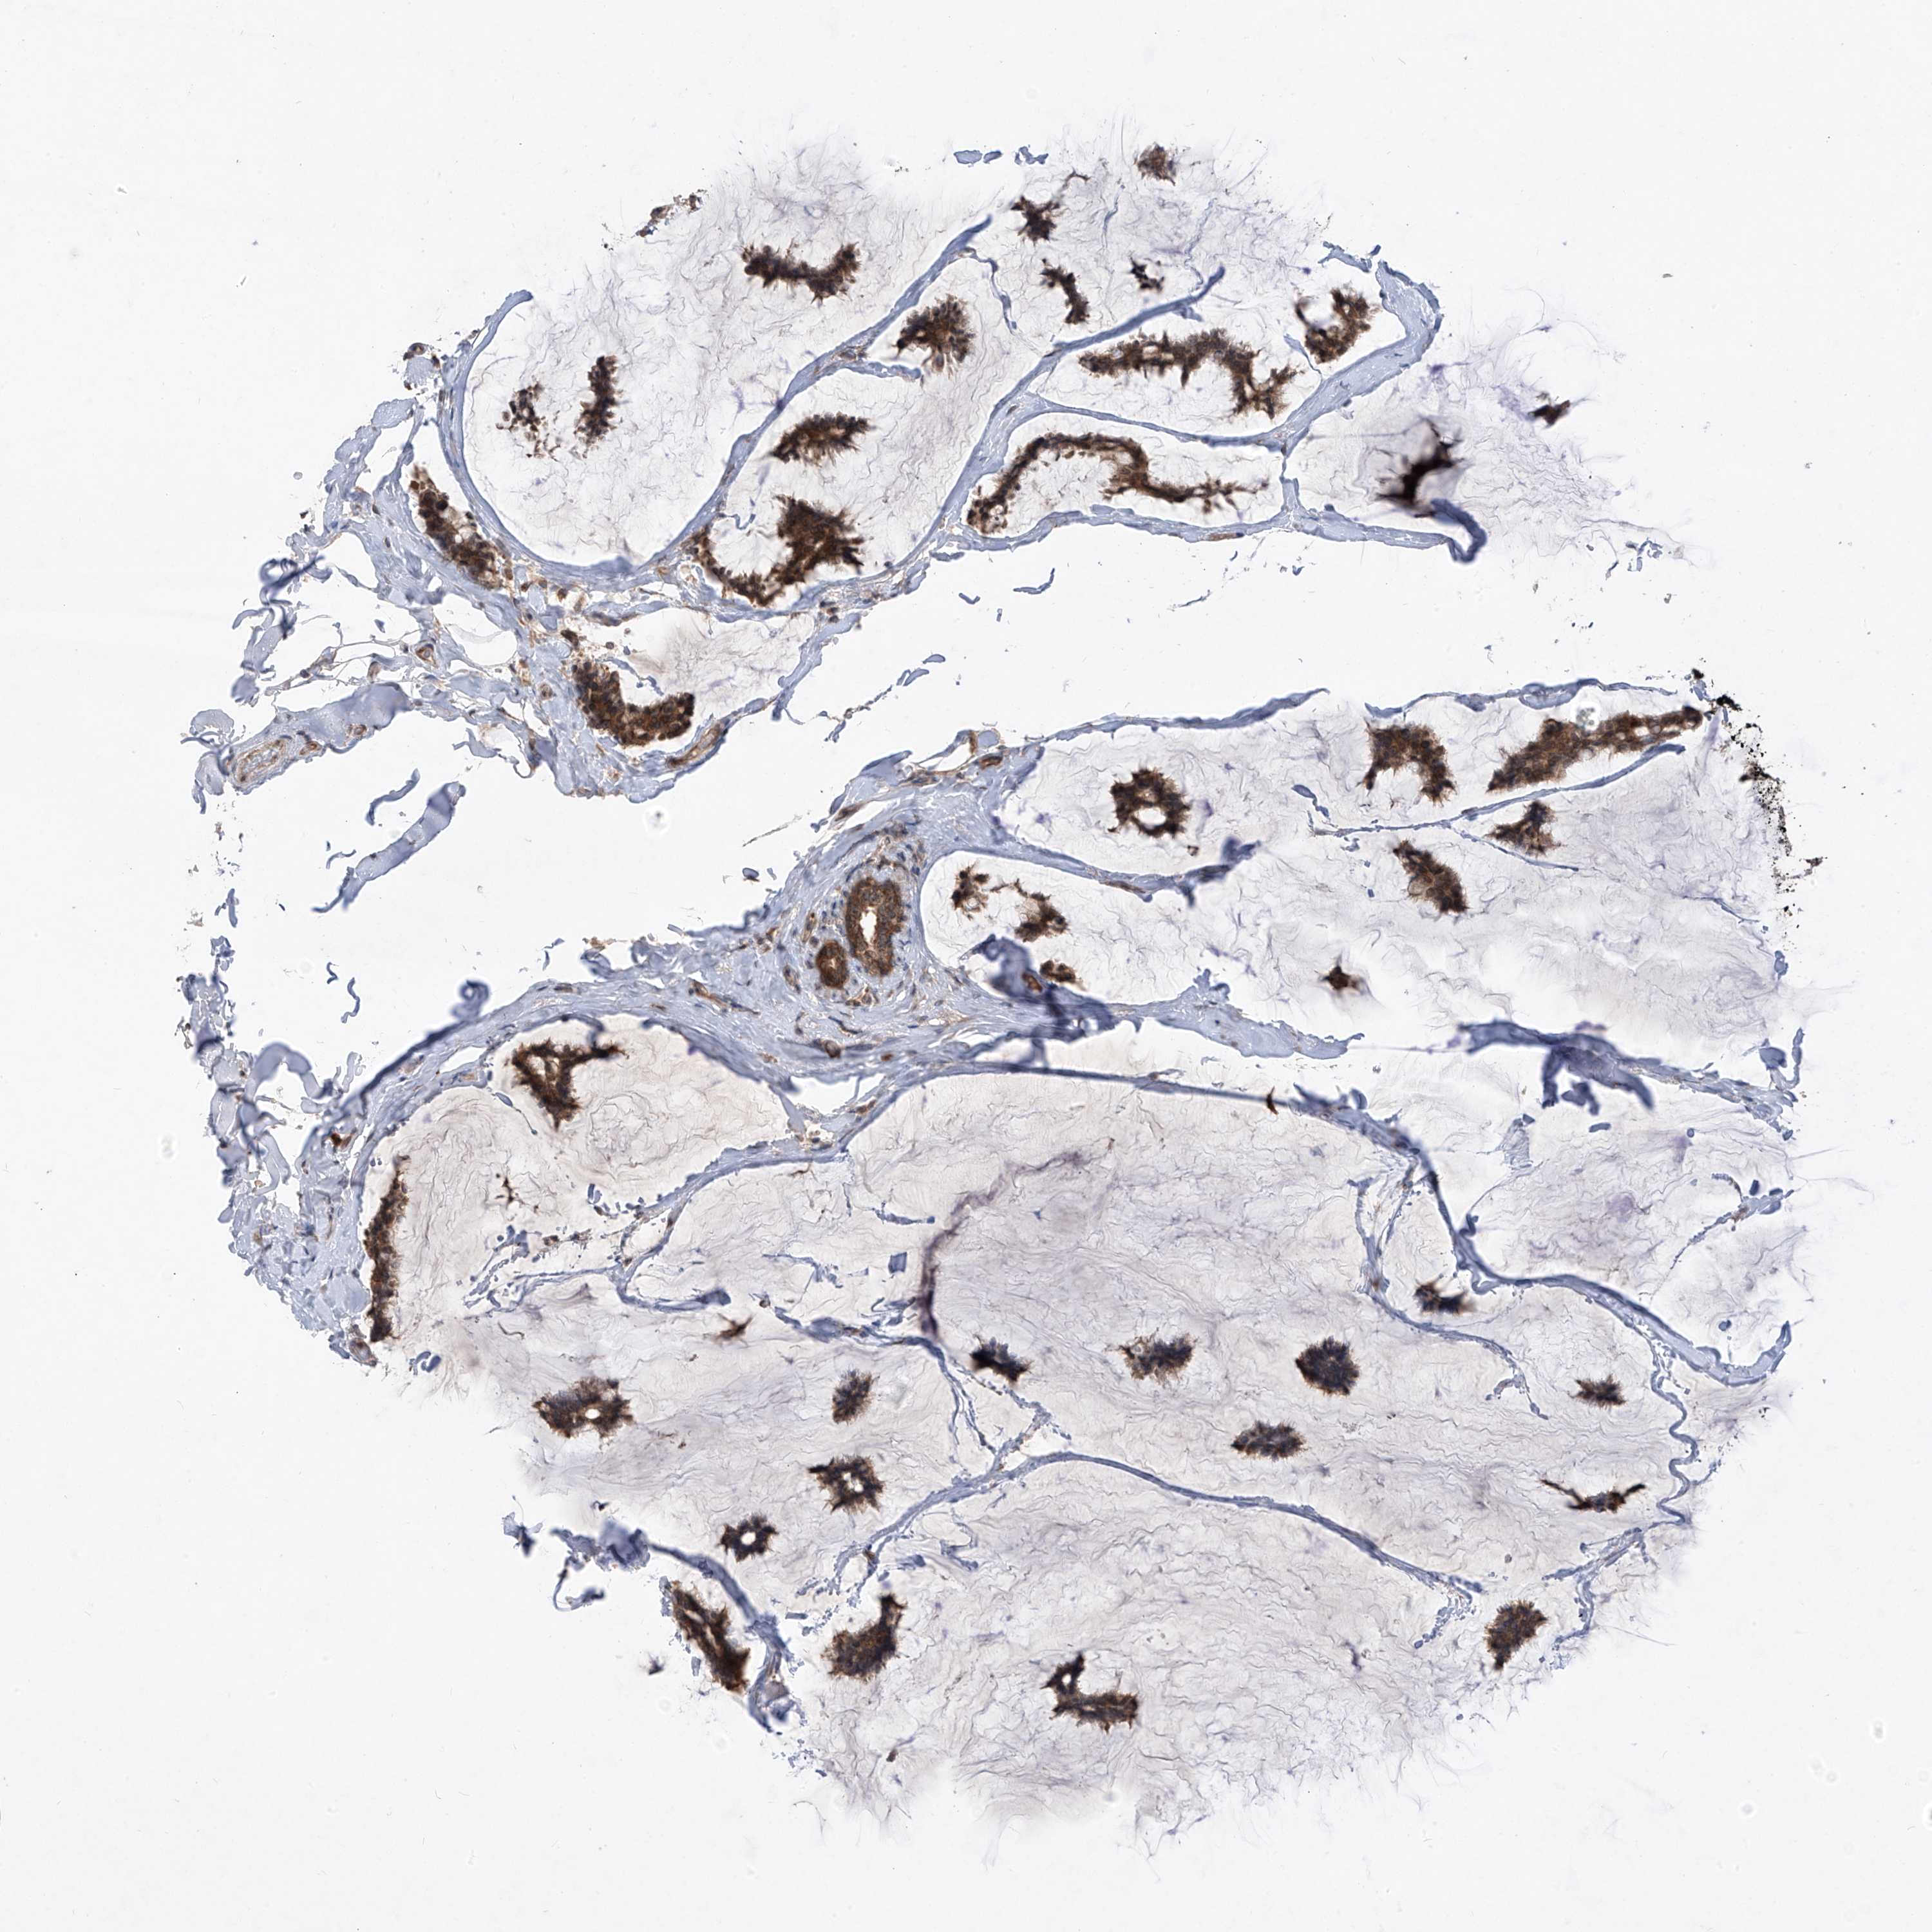

CANCER BREAST CANCER Show tissue menu

BRCA TCGA BRCA VALIDATION PROTEIN EXPRESSION